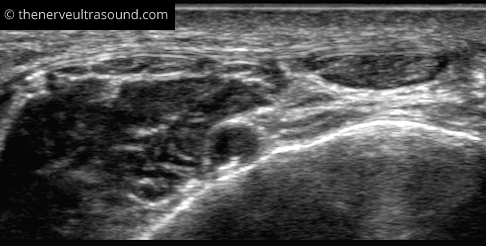

At the fibular neck, the common peroneal nerve lies close to the bone. Here it is at high risk of injury from direct compression.

Distal to the fibular neck the common peroneal nerve divides into the deep peroneal nerve and the super- ficial peroneal nerve.